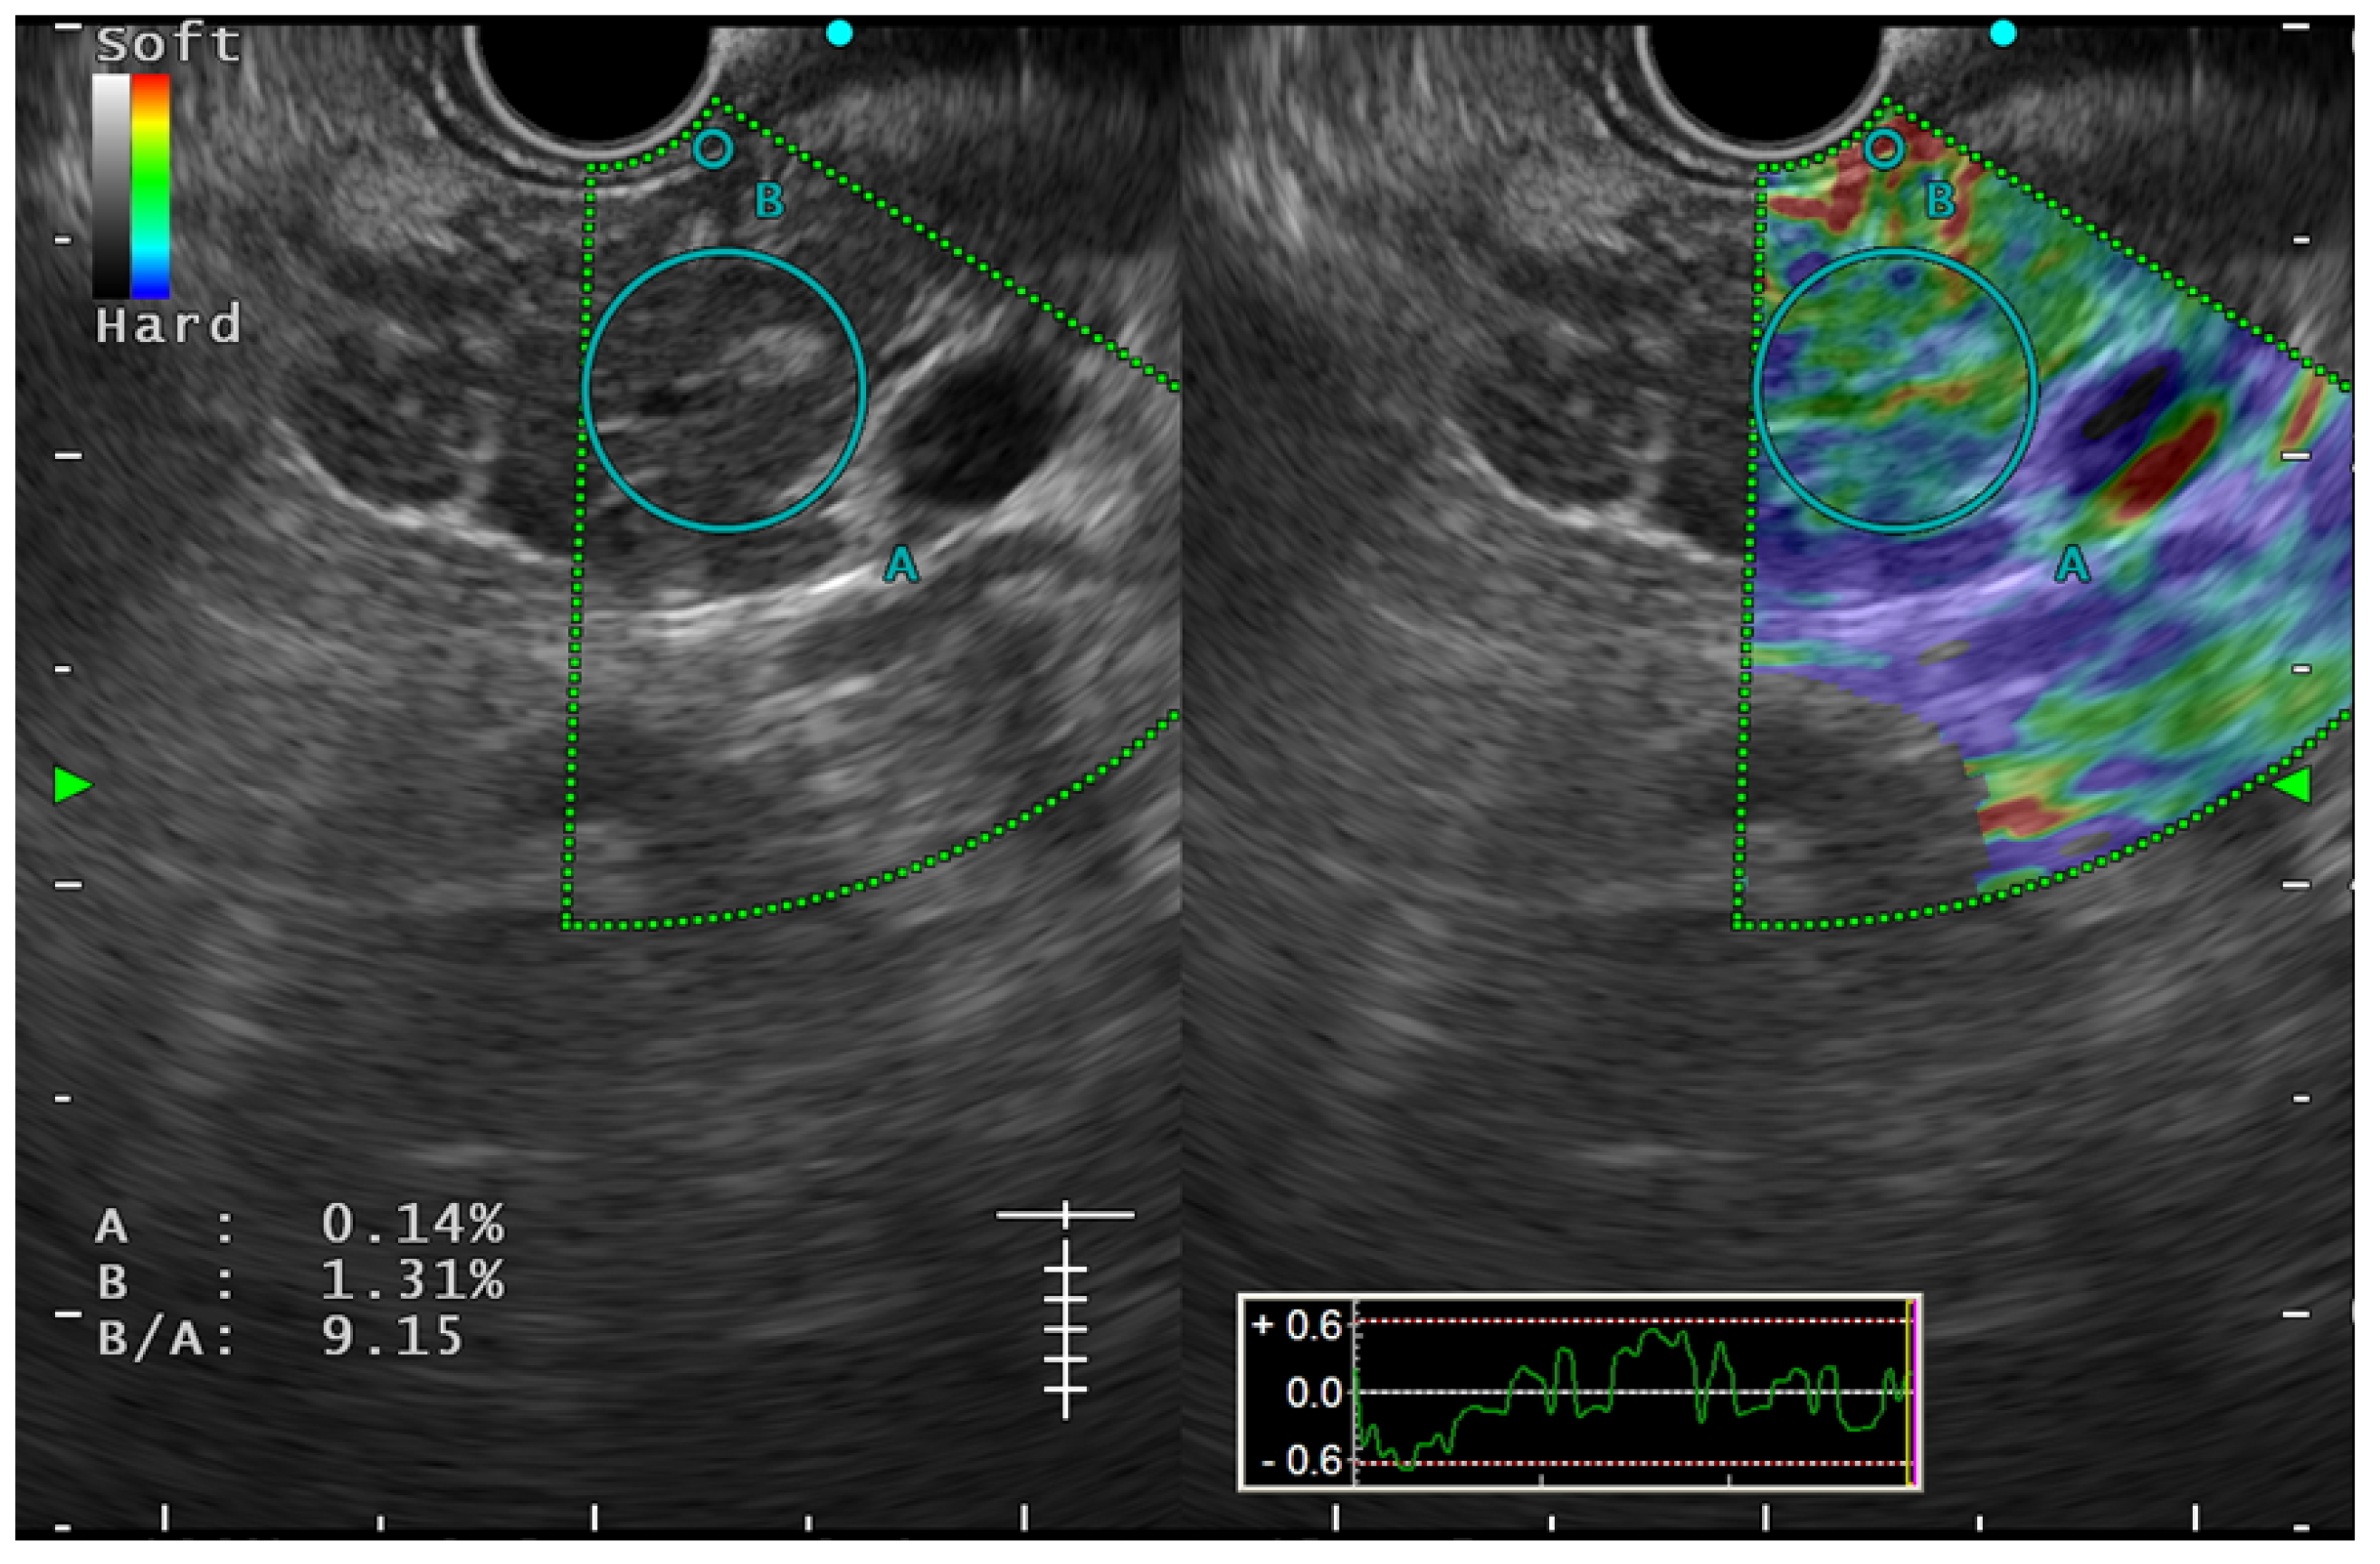

6.3. The Role of EUS Elastography in Early CP

- Iglesias-Garcia, J.; Domínguez-Muñoz, J.E.; Castiñeira-Alvariño, M.; Luaces-Regueira, M.; Lariño-Noia, J. Quantitative elastography associated with endoscopic ultrasound for the diagnosis of chronic pancreatitis. Endoscopy 2013, 45, 781–788. [Google Scholar]

- Kuwahara, T.; Hirooka, Y.; Kawashima, H.; Ohno, E.; Ishikawa, T.; Kawai, M.; Suhara, H.; Takeyama, T.; Hashizume, K.; Koya, T.; et al. Quantitative diagnosis of chronic pancreatitis using EUS elastography. J. Gastroenterol. 2017, 52, 868–874. [Google Scholar] [CrossRef]

- Domínguez-Muñoz, J.E.; Lariño-Noia, J.; Alvarez-Castro, A.; Nieto, L.; Lojo, S.; Leal, S.; de la Iglesia-Garcia, D.; Iglesias-Garcia, J. Endoscopic ultrasound-based multimodal evaluation of the pancreas in patients with suspected early chronic pancreatitis. United Eur. Gastroenterol. J. 2020, 8, 790–797. [Google Scholar] [CrossRef] [PubMed]